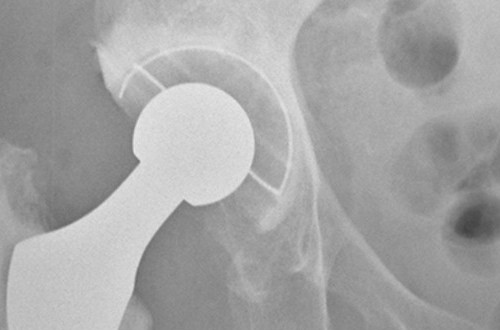

Over 3 million adults in the UK are living with severe obesity (BMI ≥40, or ≥35 with comorbidities), which raises the risk of diabetes, heart disease, cancer, poor mental health, time off work, and early death. These individuals need effective, evidence-based support. New weight loss medicines show promise, but important questions remain about long term results and value for money. For those with severe obesity, surgery is a proven and effective intervention. Until recently, it was unclear which operation offered the best outcomes for patients and the NHS, and there was no national policy on which procedure to prioritise. The landmark By-Band-Sleeve trial compared three surgical procedures—gastric bypass, sleeve gastrectomy, and adjustable gastric banding. The results are unequivocal: at three years, the Roux en Y version of gastric bypass delivered the best weight loss, the greatest health gains, and the best value for money. Smaller European studies report similar patterns, supporting these findings.